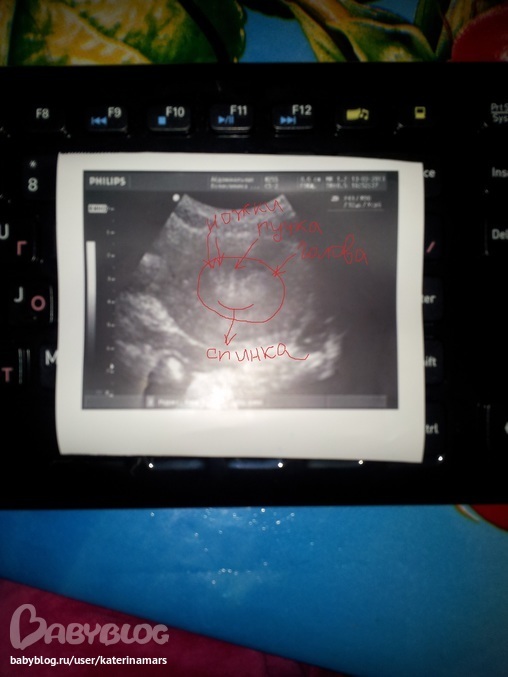

ну вот девочки, не выдержала и сходила я все-таки на УЗИ и вот мои результаты

Внимание!заключение-двурогая матка!

Уз.- ну я не вижу пока плодного яйца, рано еще!

Уз.- Матка увеличена и эндометрий очень пышный!

Уз.- Ну тут я ничего сейчас сказать не могу, тут такая картина что прям не понятно, надо будет повторить УЗИ через неделю, просто бывает когда посмотришь и видно , что -вот , например очень скоро пойдут М, а тут я не могу этого сказать, так же как и о наличии Б , одно видно точно, что матка двурогая

Уз.- ну тут явно выражена двурогая матка!

И она повернула манитор на меня и показала мне две полости "рогов" так и есть она -двурогая! Я конечно была в шоке!

Вообщем, девчёночки, незнаю что и думать, пришла домой , сходила в туалет , и обнаружила несколько капель еле розовых, животик потягивало и поясницу, но тотом ничего не было, сейчас вот сижу и внизу живота как напряг какой то и покалывания............хм.. странно, переживаю теперь чего там у меня вообще! Вообщем , если не пойдут М , то в понедельник на ХГЧ! и прикрепляю УЗИ

Девочки, перенесла фото УЗИ и смотрю на них и вижу в середине полости как голова и ручки и ножки, ахахахаххахааа, все это клиника